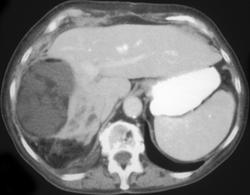

Acute Cholecystitis